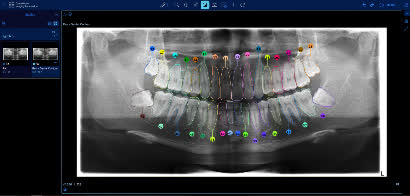

「AI+ 醫療創新」展區展示衞生署概念驗證項目「從人工智能診斷到自動化牙科圖表」,利用先進的半監督對比學習方法,以AI解讀牙科X光影像,驗證了將影像分析轉化為結構化資料,自動生成牙科圖表,並與臨床管理系統整合的潛力。展望最終成果可減少人手資料輸入、降低錯誤率,節省寶貴臨床時間,邁向智慧化、一體化牙科護理。